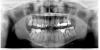

juli63 Опубликовано 14 августа, 2011 Поделиться Опубликовано 14 августа, 2011 1. 46,47,36,37,17,24,26,27 перелечивать от и до. однозначно проблемные2.каждый из этих зубов, в случае неудачи при перелечивании, может вас покинуть3. диагноз по одному только снимку не ставится. нужен осмотр конкретно каждого зуба4.см пункт 15. чтобы не было второго раза нужно сразу лечиться у грамотного специалиста6.это решается индивидуально исходя из конкретной клинической ситуации7.вкладка,коронка8.см пункт 6. составляется план лечения9. почему нет. все зависит от хирурга. лучше удалять у имплантолога. PS:на счет пломб на остальных зубах по снимку однозначно сказать сложно, но мне они не нравятся. Ссылка на комментарий

DokDent Опубликовано 14 августа, 2011 Поделиться Опубликовано 14 августа, 2011 Спасибо за ответ! Совсем глупый вопрос, ответьте пожалуйста или можно ссылку, где посмотреть... Извините, не знакома с нумерацией зубов. Что из того, что надо перелечивать - справа/слева вверху, а что - справа/слева внизу?46,47-справа внизу,17-справа вверху,36,37-слева внизу,24,26,27-слева вверху Ссылка на комментарий